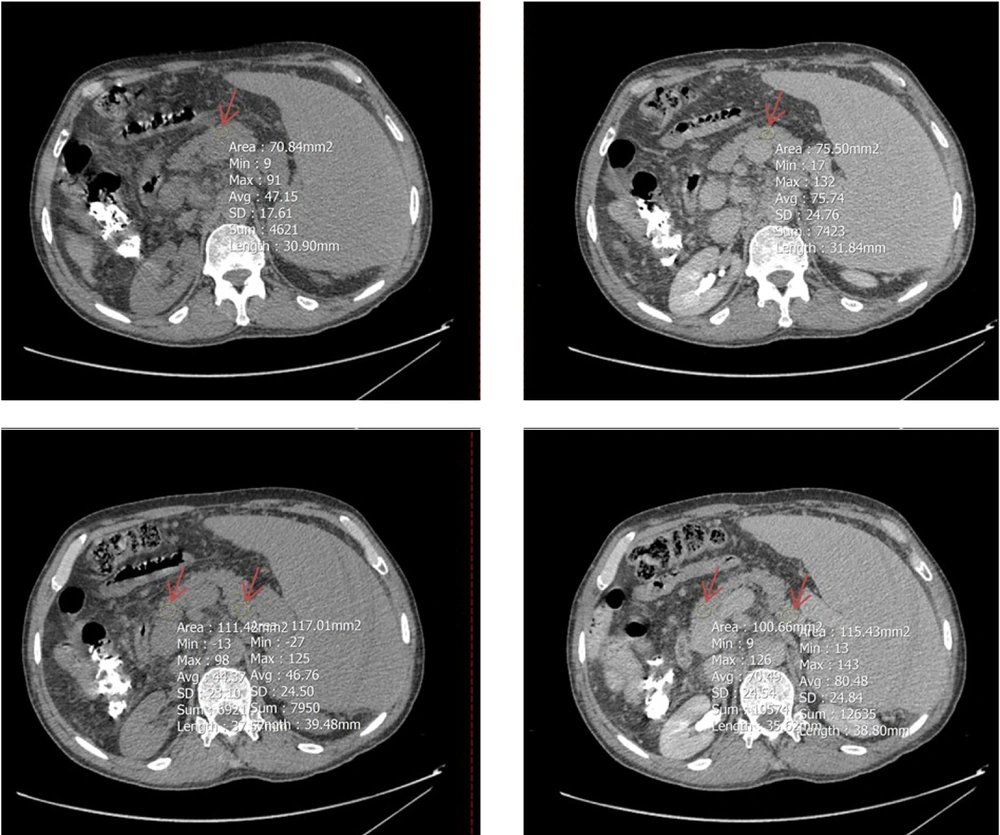

To determine mean Hounsfield units (HU) in both equilibrium and non-contrast phases, circular regions of interest (ROIs) were drawn as large as possible at specific anatomical landmarks. These included the right hepatic lobe at the level of the porta hepatis (Figure 2), the pancreas (head, body, and tail; averaged HU from the three segments was used to represent the whole organ) (Figure 3), and the spleen at its widest cross-sectional area, excluding vessels and focal lesions (Figure 2). An additional ROI with a 15-mm diameter was placed in the abdominal aorta at the level of the renal artery origin (Figure 4).

A circular region of interest (ROI, indicated by red arrow) was positioned as large as possible on Axial computed tomography (CT)-scan images (left: Non-contrast phases, right: Equilibrium phases) at three segments of the pancreas: Head and tail (two lower images) and body (two upper images); the average HU value from these parts was used to represent the entire organ.